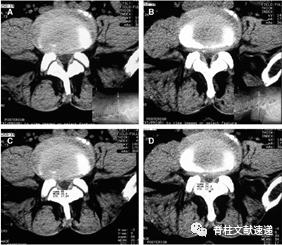

图示:L4-L5椎间盘CT。在(A)和(B)压缩之前和之后。A(C)的测量。B(D)的测量。压迫时,椎间盘膨出,黄韧带折叠,硬脑膜囊的横截面积从88平方毫米变为39平方毫米。在这种情况下,相对椎管狭窄变为伴有外部压迫的绝对性椎管狭窄。